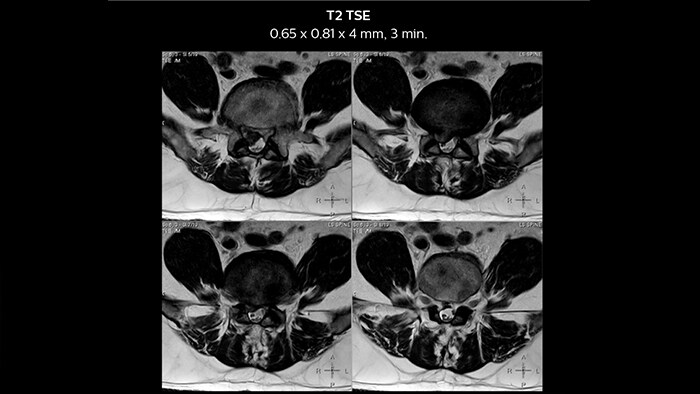

In this patient MRI images show spondylotic degenerative changes in the lumbar spine, in view of the osteophyte, disc desiccations and Sc hmorl’s nodes with lumbarization of S1, post-laminectomy changes at L5-S1 and S1-S2 levels with disc protrusion and extrusion, and diffuse disc bulges from L3-L5 with nerve root compression.